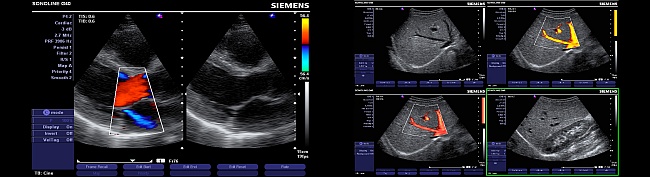

Die Farbduplex-Sonographie ermöglicht sowohl akustisch als auch durch Farbkodierung Blutfluss in den Gefäßen (Arterien und Venen) farblich sichtbar zu unterscheiden.